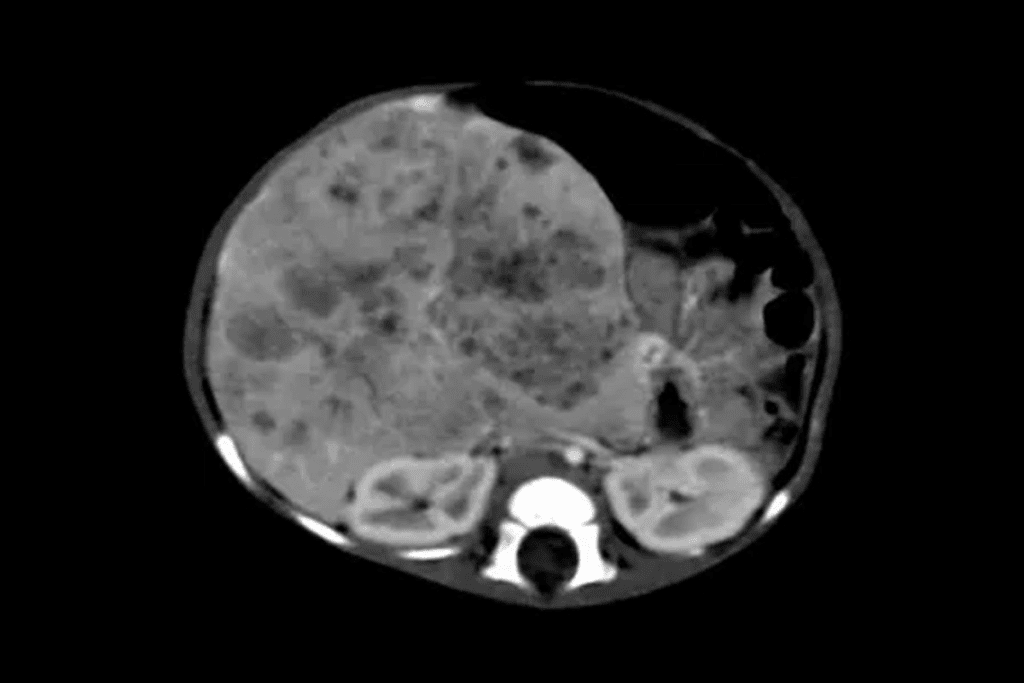

Advanced Imaging Techniques for Measuring Hepatoblastoma

We use top-notch imaging to check the size and spread of hepatoblastoma tumors in the liver. MRI and CT scans are key in measuring these tumors accurately.

Measuring hepatoblastoma right is key for treatment planning. When tumors are found in multiple sites in the liver, knowing their size and location is critical. This helps in planning surgery and understanding the patient’s outlook.

Clinical Implications of Multiple Tumor Sites

Having tumors in multiple sites makes treatment more complex. It needs a detailed plan for surgery and chemotherapy. Advanced imaging helps pinpoint the tumors’ exact spots and sizes, leading to a more personalized treatment.

When there are multiple tumor sites, the team must think about the liver’s function and how treatment might affect the patient’s life. Our team of experts works together to create a detailed treatment plan.

Advanced imaging is not just for the first check-up. It also helps track how well treatment is working. This allows for changes in the treatment plan as needed. This flexible approach is key to better outcomes for patients with hepatoblastoma.